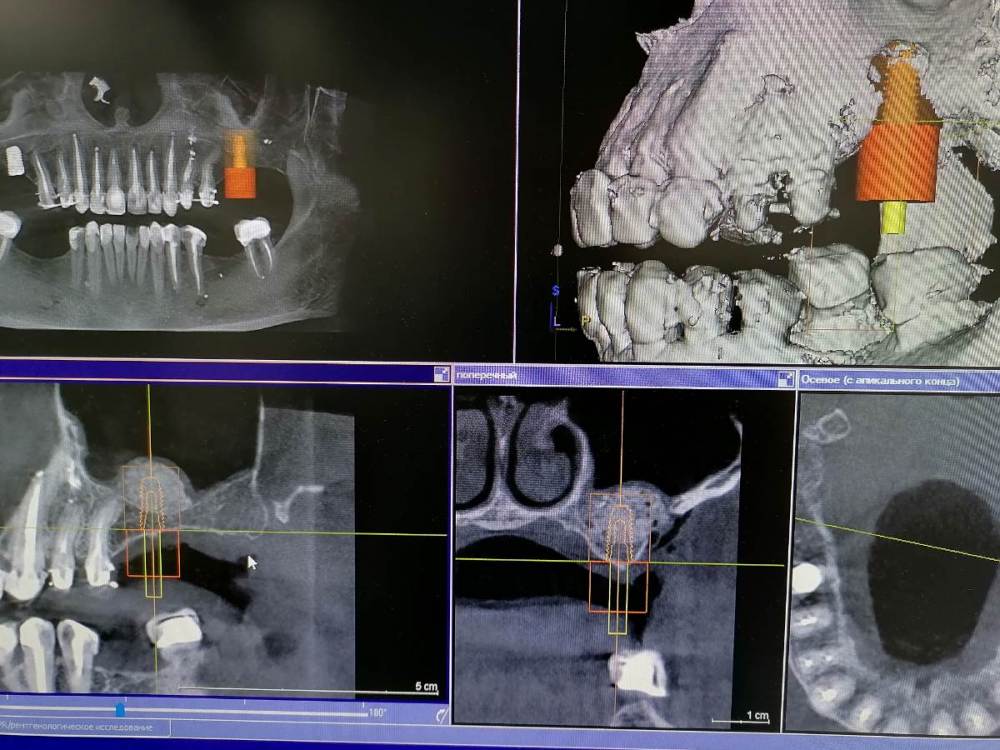

Ponchik Опубликовано 26 марта, 2021 Поделиться Опубликовано 26 марта, 2021 Планировалось: удаление 2.5 зуба, синуслифтинг и вторым заходом имплантация 2.6, 2.7 Получилось: ортопед решил оставить 2.5, одел временную. Хирург (я) решил, что от кривулины 2.5 он будет при имплантации убегать и т.д. и поставит имплантант в области 2.6 (ближе к 2.7) ну и соответственно 3.7 парой бугров какой-то контакт себе найдёт и будет всем счастье. И сделал синуслифтинг для 2.6. Оказалось, что ортопед таки всё ещё хочет имплантант в позиции 2.7. Зря я поумничал. Теперь думаю в какие сроки делать окно в области 2.7? Ждать полгода? ПыСы : В области 1.6 имплантант ставил лет 5-7 назад кто-то, где-то. Он в кости на 3-4мм. Надо будет убрать, но пока не про это. Скрытый текст Ссылка на комментарий

Ponchik Опубликовано 26 марта, 2021 Автор Поделиться Опубликовано 26 марта, 2021 2 часа назад, АнтонТЛТ сказал: Какой размер планируется в области 27? Думаю без фанатизма - 4.5-10 (4.5-8 если пробовать закрытый) Ссылка на комментарий

Ponchik Опубликовано 27 марта, 2021 Автор Поделиться Опубликовано 27 марта, 2021 12 часов назад, Raystom сказал: @Ponchik а чем Вас смущает закрытый синус? Я его не делал ни разу, нет уверенности, что не порву Шнайдерову. Точнее порву и не замечу, натолкаю туда графта и буду потом его из носа с пациентом высмаркивать. Когда просто на 1-1.5 мм. стукнуть, это часто делаю. Но там порвал не порвал - пофиг. А вот с материалом ? Сколко раз стучал, пробовал увидеть, там мембрану - ни черта не видно. Если ну очень сухо видишь её чуть-чуть, но целая она там или нет не видно. При открытом налил физ.раствора и видно - целая или нет, а при закрытом контроля нет Ссылка на комментарий